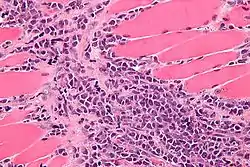

![]() صورة مجهرية للساركومة النخاعية ضمن العضلة. صبغة H&E. صورة مجهرية للساركومة النخاعية ضمن العضلة. صبغة H&E. | |